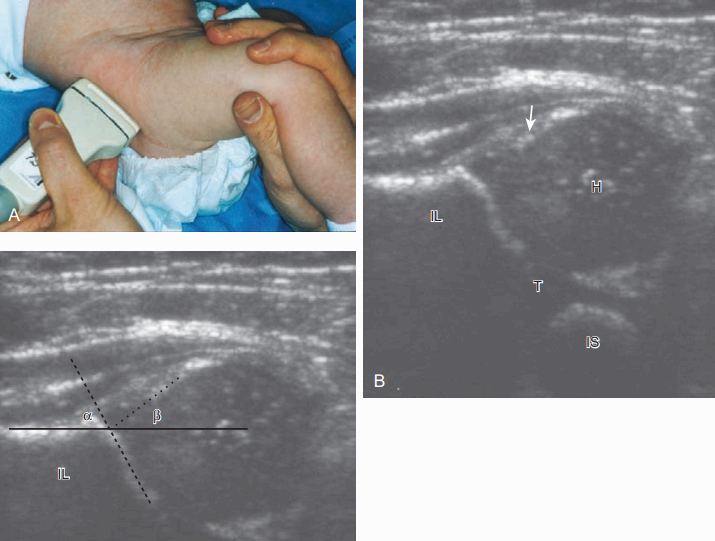

엉덩관절 형성이상을 위한 초음파 검사 기법에는 여러 의견들이 있다. 한 방법은 넙다리뼈머리의 위치와 측정(measurement)을 중요시하지만, 다른 방법은 Ortolani와 Barlow 수기를 이용하여 위치와 안정성에 대한 동적 검사를 강조한다. 어떠한 방법을 이용하던지 간에 최소한 다음의 검사를 포함시킨다.

(1) 관상중립(coronal neutral) 또는 관상굽힙자세(coronal flexion position)에서 적절한 스트레스와 측정을 시행하는 것과,

(2) 가로축 굽힘자세(transverse flexion position)에서 스트레스를 가한 검사와 가하지 않은 검사를 반드시 포함하여야 한다. 엉덩관절 형성 이상의 초음파 검사는 몇 가지 단계로 나뉜다. 첫 번째 단계는 중립자세에서의 관상영상(엉덩관절은 약간 굽힌 상태)이다. 이 자세에서 얻은 영상은 손가락 위에 달걀이 놓인 것과 비슷하여, 편평한 엉덩뼈 표면을 따라 그은 연장선(이를 기준선이라 함)이 넙다리뼈머리를 적어도 50% 이상 덮고, 절구 a(알파) 각은 60도 이상이다. 절구 a각은 기준선이 절구천장선(acetabular roof line)과 이루는 사이각을 말한다. b(베타) 각은 절구 테두리를 지나는 경사선(inclination line)이 가쪽엉덩뼈 기준선과 이루는 사이각을 말한다. 골화 된 절구와 넙다리뼈는 소리그림자를 동반하는 높은 에코로 보이며, 넙다리뼈머리의 골화 되지 않은 부분과 세 갈래 연골(triradiate cartilage)은 얼룩덜룩한 낮은 에코로 보인다. 두 번째 단계는 엉덩관절을 굽힌 상태에서의 관상면이다. 이 자세에서는 탐촉자를 세 갈래 연골 뒤에 놓고, 환아의 다리를 잡고 앞에서 뒤로 스트레스를 가하여 넙다리뼈머리가 뒤쪽으로 탈구되는지를 검사한다. 세 번째 단계는 환아의 다리는 두 번째 단계와 같게 하고, 탐촉자를 넙다리뼈에 평행하도록 돌려놓는다. 다리를 잡은 손으로 엉덩관절을 밀면서 스트레스를 가한 채로 엉덩관절을 모음(adduction)시키면서 동적검사를 하고(Barlow test), 다리를 잡아당기면서 엉덩관절을 벌림(abduction)하여(Ortolani test) 엉덩관절이 탈구되는지, 아니면, 탈구된 넙다리뼈머리가 원래의 자리로 되돌아오는지를(relocation)를 검사한다.